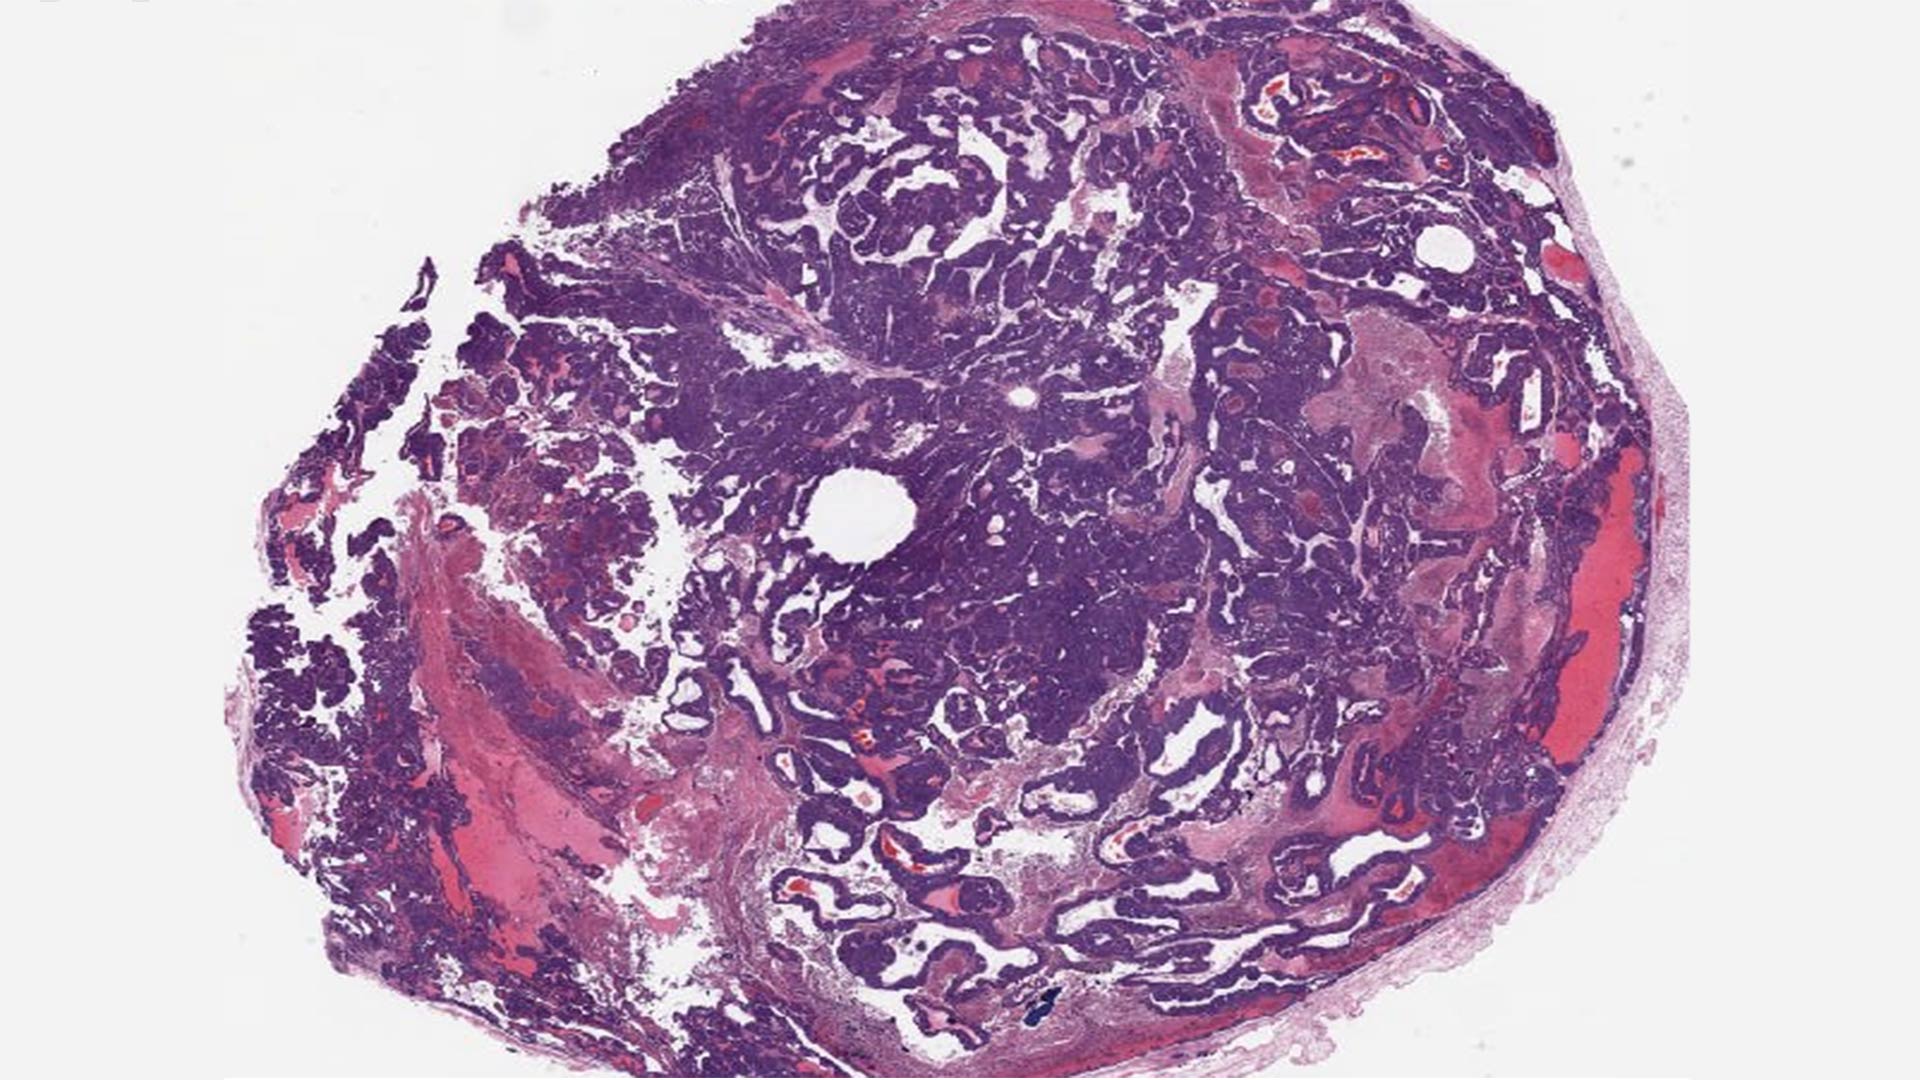

Previous research had found that knocking out BPTF slows breast cancer growth but doesn’t stop tumors from forming. As such, pharmaceutical companies didn’t see much promise in the protein. However, Ciccone and his lab-mates, graduate student Dhivyaa Anandan and postdoc Deeptiman Chatterjee, saw untapped potential. To learn more, they bred a classic breast cancer mouse model with a BPTF knockout mouse. To their surprise, they found the tumors in the crossbred mice remained ER+ throughout their development.

“There isn’t any mouse model that maintains a hormone-positive cancer throughout the cycle of the tumor,” Ciccone said. When treated with tamoxifen, one of the most common hormone therapies for ER+ breast cancer, the tumors were “responding and not growing,” he said. “That’s when we realized that we were onto something.”

The team tested a combination of BPTF loss and tamoxifen in organoid systems, human breast cancer cell lines, and mouse models resistant to hormone therapy. In all cases, the combination restored sensitivity to treatment. “Our work highlights biological mechanisms that are not only very fascinating, but translatable,” Chatterjee said.